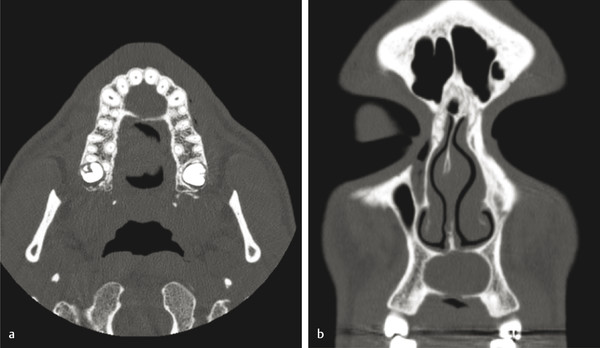

Finally, the nasopalatine duct cyst (NPDC) is a nonodontogenic developmental cyst that is usually found incidentally in the anterior maxilla in the area of the incisive canal. It can become painful, especially if secondarily infected. Radiographically, on an occlusal plain film radiograph, one finds a midline heart-shaped unilocular radiolucency. The lesion often is symmetric and is present in the anterior maxilla along the length of the incisive canal (Fig. 9‑5). Treatment comprises enucleation and curettage, with recurrence being very rare.